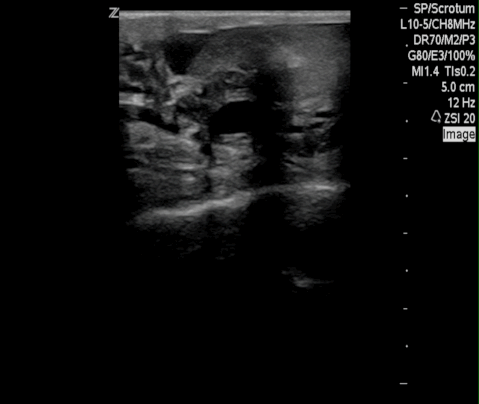

Filarial Dance Radiology Case Radiopaedia Org

Filarial Dance Sign On Scrotal Ultrasound W Bancrofti This Grepmed

Composite Of Scrotal Ultrasound Findings In Different Men Before Download Scientific Diagram

Ultrasound Image Showing Clusters Of Small Echogenic Structures Within Download Scientific Diagram

Scrotal Filariasis The Importance Of Filarial Dance Sign In Scrotal Ultrasound

Scrotal Ultrasound Shows The Characteristic Filarial Grepmed